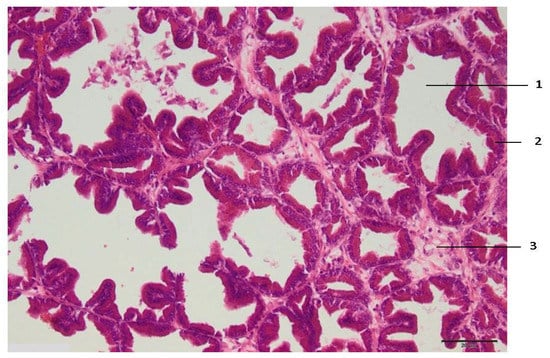

Figure 2.

Histologic zone II of the prostate lesion: 1—alveolar gland of the prostate; 2—secretory epithelium with dark pycnotic nuclei; 3—connective tissue edema. Microtome-cut sections of prostate samples were stained with hematoxylin and eosin.

Zone I makes direct contact with the electrode and is always larger than the electrode tip area. Zone II is the application zone adjacent to the thermal electrode (Figure 2). Acinar prostate epithelial cells are in a normal shape, with pronounced eosinophilic cytoplasm and dark pycnotic nuclei (onset of necrosis). Very prominent connective tissue edema and non-striated muscle cells with degenerative lesions are observed.